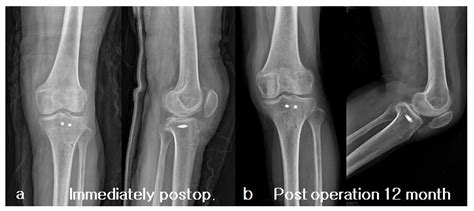

• X-Rays: X-rays provide detailed images of bone structures, allowing for the identification of fractures and other bony abnormalities.

• CT Scans: Computed Tomography (CT) scans provide high-resolution images of bone structures, useful for assessing complex fractures and planning surgical interventions.